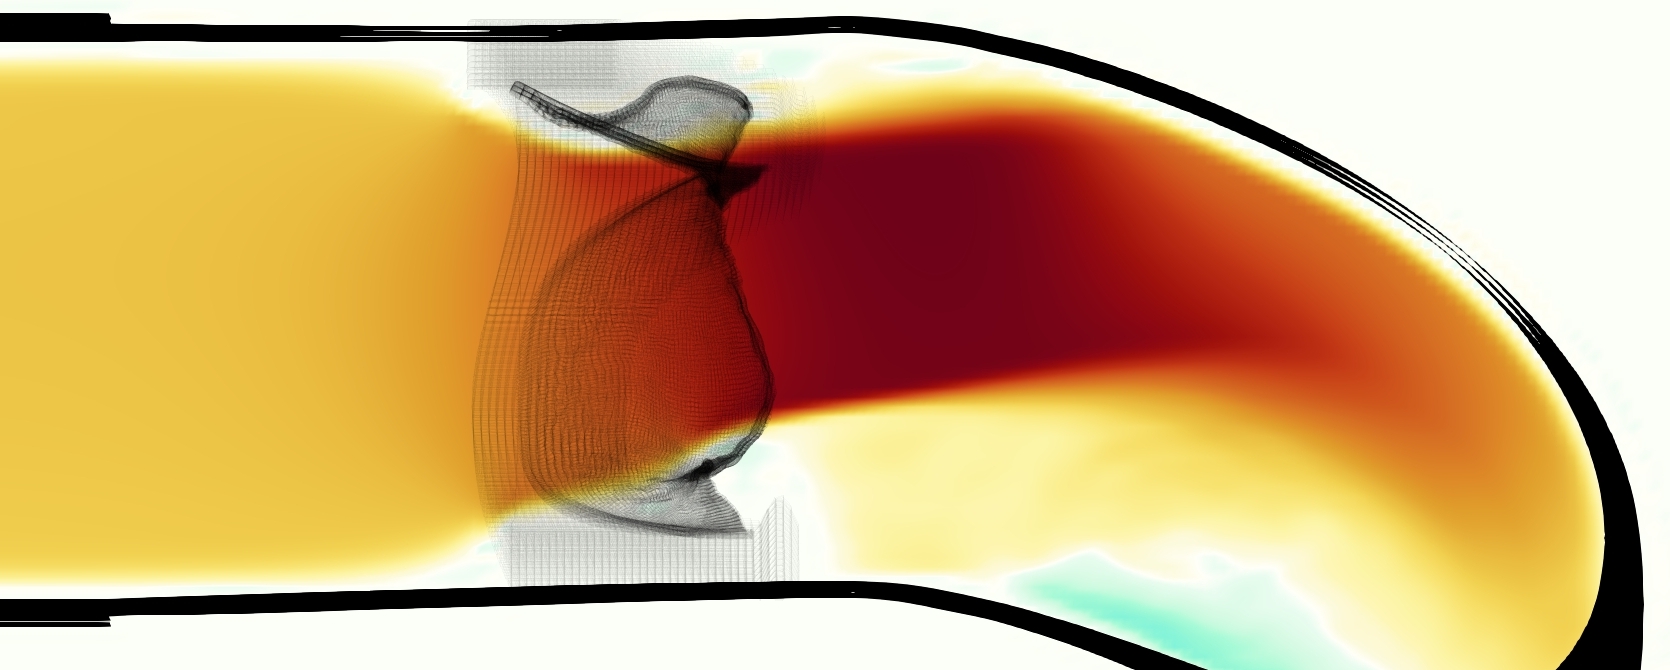

The emergent hemodynamics showed excellent qualitative agreement with experiments. Slice views of the axial component of fluid velocity ( component) in the sagittal plane that cuts through the center of the vessel, parallel to the flow direction, are shown in Figure 5. The flow in both the simulation and the experiment began to accelerate at the same time, with a jet forming through the open valve leaflets. The velocity, angle, and shape of the jet agreed well between the two cases during systole. The simulation captured the slight upward angle of the jet, which was not fully centered in the vessel. It also matched the location where the jet impacts the wall and the slower speed of the jet as it turns with the MPA downstream. As the flow decelerated, the fluid along the interior curve of the vessel reversed first while forward flow persisted where the jet was strongest, as seen in both the simulation and experimental results.

In both the experiment and the simulation, a separation region of reverse flow developed along the interior curve of the vessel under the core jet through the valve. The reverse flow began to develop at the same time in the cardiac cycle and grows throughout systole. The simulation lacked reversed flow in the entire region where reversed flow was present in the experiment, but this region developed some flow separation and had much slower flow than elsewhere in the vessel. Thus, the simulation captured that this is a distinct region from the core jet through the valve opening. There was a smaller amount of slower and slightly reversed flow along the outer curve of the vessel, close to the valve annulus and scaffold support. This region was well-matched between the experiment and the simulation.

A comparison between the phase-averaged velocity resampled onto the MRI grid, the phase-averaged velocity without resampling, the instantaneous flow field without resampling and the MRI velocity field is shown in Figure 8. The coarser resolution is visible as a “stair-stepping” or “pixelated” effect on the phase-averaged resampled velocity, whereas the edges of the jet are more smooth in the phase-averaged velocity with no resampling. Otherwise, the resampled velocity appears qualitatively similar to the phase-averaged velocity with no resampling. Fine scale features were present in the instantaneous field that were lost in the phase-averaging and resampling process. There was more variation in the local velocity of the center of the jet and local areas of high velocity at the edges of the jet that suggested vortices. Vortical structures adjacent to the jet and in the areas of reversed flow were apparent. These comparisons suggest that 4D flow MRI data may lose substantial fine-scale flow features in the flow field via phase-averaging.

The simulated velocity fields showed excellent qualitative agreement with the experimental velocity. Many features of the flow that were present in the experimental measurements also appeared in the simulations, including a large jet which angled up downstream of the valve and the appearance of a triangle-like shape in the jet. A recirculation zone appeared downstream, though the precise region of recirculation showed only some agreement at some points in time. We prescribed the experimentally measured pressures (subject to minor processing as described in Section 3.3), and the emergent flow rates matched those of the experiments.

The simulated velocity fields also showed quantitative agreement with the experimental velocity. The entire flow domain interior to the vessel showed relative error of 30% on velocity magnitude and 36% on the component of velocity during mid-systole. While this certainly leaves room for improvement, we are not aware of any other studies comparing simulated flow around heart valves to experiments that compute relative error on the entire flow field. Similar results were found at and 0.625 cm, and slightly higher relative error downstream at 1.25 cm. The nondimensional streamwise momentum, represented by , was extremely similar in simulation and experiment.

Of potential future interest, the phase-averaged, resampled velocity showed substantial differences from the instantaneous velocity fields, with more variation in local fluid velocity and more fine scale vortical structures visible in the simulation (Figure 8). This points to an advantage for simulations: since 4D flow MRI data is fundamentally phase-averaged, once validated, simulations provide a richer dataset when these instantaneous fluid features are of interest.